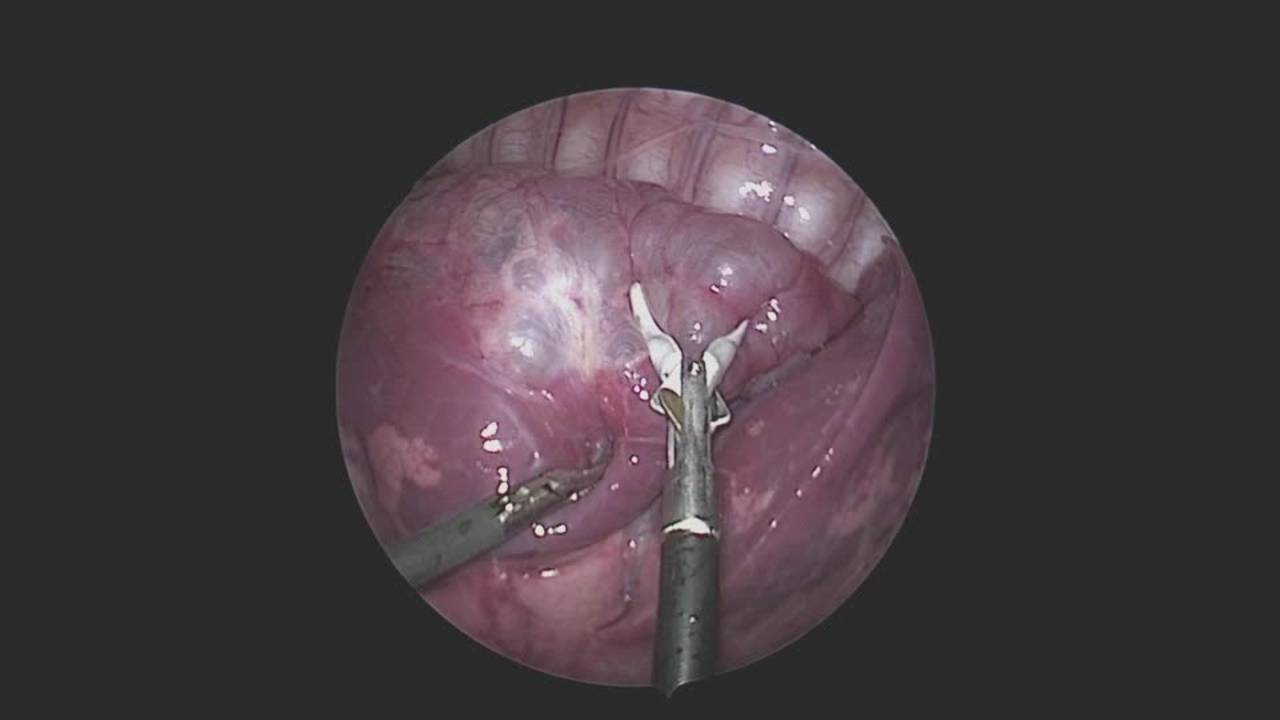

Thoracoscopic Right Lower Lobe Cystic Lesion Excision: Update Course 2014

Dr. Steve Rothenberg, Chief of Pediatric Surgery at Rocky Mountain Hospital for Children, Denver, Colorado, presents the topic of congenital cystic lung lesions. Topics discussed include asymptomatic congenital lung lesions, thoracoscopic lobectomy, post-operative course, as well as when and why to operate.